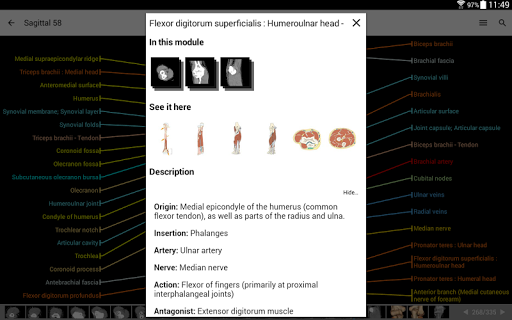

-In the details view of an anatomical structure related terms are now displayed

-Within the details view of an anatomical structure, a pin now points the related structure in all present images